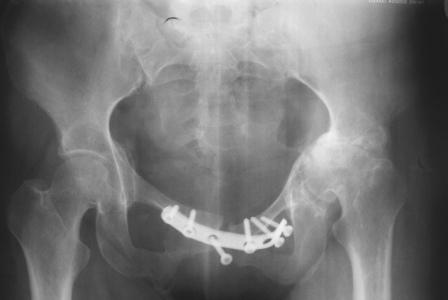

Уважаемые коллеги! Пациентка 32 года с застарелым повреждением таза, после остеосинеза лонного сочленения пластиной. Посоветуйте с выбором тактики и методик лечения.

Получила травму в феврале 2004г в г.Лобытнанги ЯНАО Тюм.обл. Через неделю после поступления выполнен остеосинтез лонного сочленения пластиной. 1,5 месяца на скелетном вытяжении. В последующем ходит при помощи костылей с нагрузкой на правую ногу. Имеется нестабильность половин таза, неправильно-консолидированный перелом левой вертлужной впадины, невропатия седалищного нерва слева. В результате невропатии седалищного нерва сформировалась эквинусная установка левой стопы,парестезии по подошвенной поверхности.

Направлена к нам для устранения патологической установки стопы и эндопротезирования левого тазобедренного сустава, также имеется миграция шурупов пластины, фиксирующей лонное сочленение.

Клинически: ходит на костылях с нагрузкой на правую ногу. Левая стопа в эквинусе. Осевая нагрузка на левую н\конечность болезненна в области левого тазобедренного сустава, при прикосновениях к подошвенной поверхности стопы у пациентки чувство зжения. В левом коленном суставе полный обьем движений, в левом тазобедренном резко ограничено отведение и ротация, укорочение левой н\конечности на 2,5 см. При полипроекционной и функциональной Р-графии выявлена нестабильность левого КПС и лонного сочленения, консолидированный в порочном положении поперечный оскольчатый перелом левой вертлужной впадины с центральным смещением головки бедра. Нами выполнена коррекция деформации левой стопы. Планируется выполнить введение 2 канюлированных илиосакральных винтов слева, реостеосинтез лонного сочленения реконструктивной пластиной, после заживления ран - тотальное эндопротезирование левого тазобедренного сустава.

Вопросы: 1. достаточно-ли предпологаемой фиксации тазового кольца, может быть добавить аппарат внешней циксации;

2. сроки установки эндопротеза;

3. методика установки вертлужного компонента.